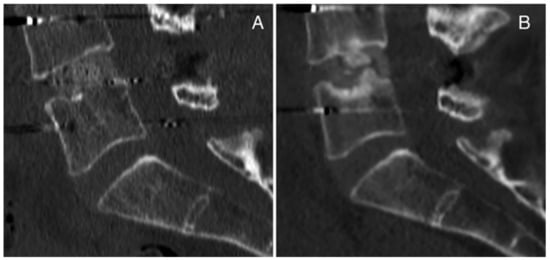

3.8. Representative Cases of Complications from Our Institution